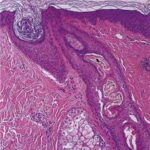

Traction Alopecia Traction alopecia is another type of mechanical alopecia, usually resulting from a variety of hair-styling practices, particularly in African-Americans, that includes tight braids, corn rows, straightening, and the use of sponge rollers . Hair follicle injury is similar to that produced in trichotillomania, but in traction alopecia there are differences that relate to the use of less force over a greater period of time (194). Traction alopecia is often classified clinically and histologically as "early" and "late" disease . In early disease, tension on hair follicles exists over the course of months to a few years, sometimes presenting as a traction folliculitis with perifollicular erythema and pustules . In late disease, hair is subject to traction over many years. In early disease, discontinuation of the abnormal forces on the hair leads to regrowth of hair, but in late disease, follicles are lost, producing a permanent alopecia. Early and late disease are commonly found together in the same patient; as permanently scarred areas develop (late disease), terminal hairs at the periphery are used in styling, becoming the new target of traction (early disease) (. Occupationally related traction alopecia has been reported due to wearing of a nurse's cap, occurring at the site of pin placement used to secure the cap . Histopathology. In early traction alopecia, the histologic findings are similar to those of trichotillomania, albeit more subtle (194). For instance, the density of follicles is normal, with a normal number of vellus hairs. Premature conversion of anagen hairs to catagen occurs, resulting in an increased number of catagen and telogen follicles. Pigment casts and trichomalacia are sometimes found, although less often than in trichotillomania. Inflammation is absent. |

outnumbering terminal follicles. In late |

disease, the pathology shows an "end-stage" scarring alopecia, a histologic picture shared by many forms of permanent alopecia at an advanced stage. Pigment casts and trichomalacia are not seen in late traction alopecia. |